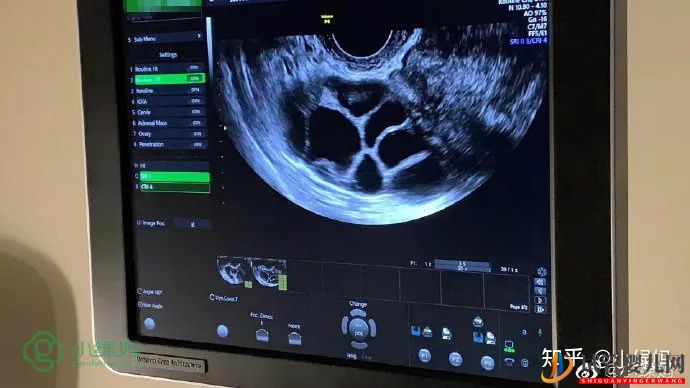

7月2 号,爱心妈妈跟陆妈妈一起在诊所移植。

7月12号,Cathy验孕成功!7月14号陆妈妈验孕成功!希望陆妈妈一切都顺利~